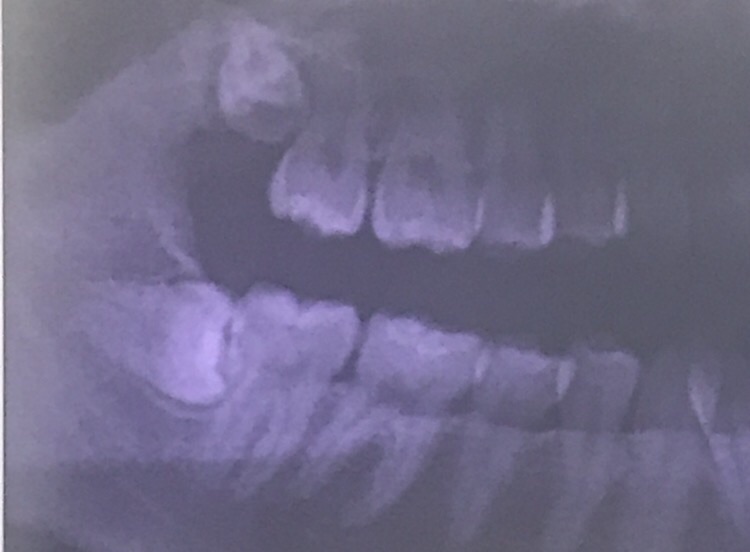

抜いたのは上右第一小臼歯と下右第二小臼歯。

上の前から4番目と下の前から5番目です。

上左右第一小臼歯、下左第一小臼歯、下右第二小臼歯 計4本の抜歯です。